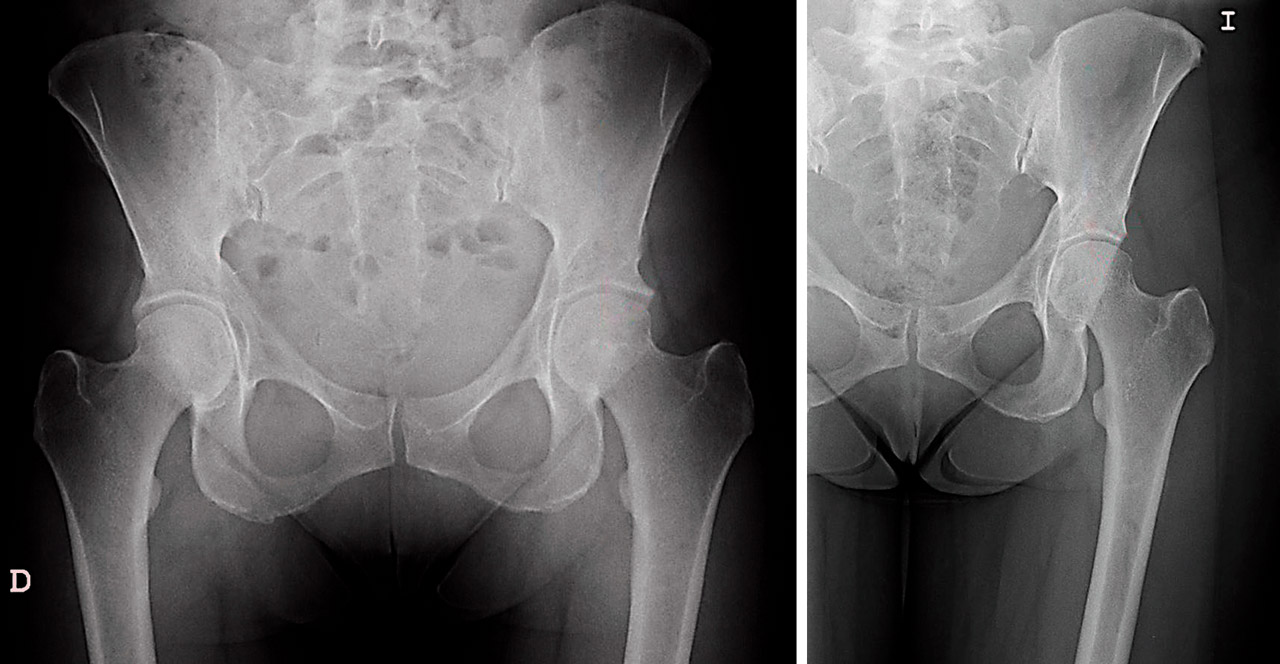

El pinzamiento de tipo PINCER se produce cuando una cabeza femoral normal se articula con un acetábulo anómalo que produce una cobertura excesiva, frecuentemente por retroversión o por la presencia de estructuras óseas como osteofitos. En estos casos, se produce un auténtico atrapamiento del labrum por este borde acetabular aumentado(1)(2). El conflicto femoroacetabular (CFA) de tipo PINCER fue descrito en 1999 como complicación tras la realización de osteotomía periacetabular(1). En general, el pinzamiento de tipo CAM se da con más frecuencia en hombres jóvenes deportistas, mientras que el tipo PINCER se da con mayor frecuencia en mujeres deportistas y de edad media(3).

El abordaje por artroscopia de los procesos de CFA de tipo PINCER, especialmente de tipo global, reviste ciertas particularidades que vamos a analizar. Para la artroscopia de cadera es importante obtener una adecuada distracción articular, ya que facilita la colocación de los portales y la movilidad intraarticular. Por ello, las condiciones que dificultan el acceso intraarticular constituyen una contraindicación relativa de este tipo de técnica(2). La dificultad de acceder al compartimento central (CC) de los casos de tipo PINCER radica precisamente en la frecuente asociación entre el obstáculo que supone la presencia de un fragmento o protrusión ósea y/o el labrum calcificado u osificado, junto a la propia inestabilidad del rodete avulsionado. Así, la tracción que se ejerce consigue predominantemente un efecto de separación en el trasfondo del acetábulo, pero no permite una adecuada distracción del borde acetabular (distracción asimétrica), dificultando por ello, en gran medida, el acceso intraarticular(4).

Antes de iniciar nuestra cirugía, deberemos tener en cuenta que la resección inadecuada de formaciones que ocasionan un CFA de tipo PINCER localizado en el borde acetabular (PINCER en retroversión o displasia, os acetabuli, avulsión de espina iliaca anteroinferior) puede generar complicaciones descritas de subluxación-luxación o rápido progreso hacia la artrosis(9)(10)(11). Deberemos realizar, para evitarlo, una medición preoperatoria y tener en cuenta el ángulo de cobertura acetabular resultante de la intervención, considerando como signo de mal pronóstico que este sea finalmente de carácter displásico.

Para llevar a cabo la resección de las formas con exceso de cobertura, seguimos los conceptos de planificación propuestos por Matsuda(15). Así, dibujamos sobre la pantalla del intensificador el patrón de la zona de resección en la proyección anteroposterior (AP), como propugna Matsuda(15), pero también lo hacemos en la axial. Ello nos permite definir mejor la resección anteromedial y la superolateral. Iniciamos la resección de la zona superior y anterior de más fácil acceso, lo que además nos permitirá ir ampliando la resección. Dirigimos esta primero hacia la zona más anterior y medial, y después a la más lateral y posterior. Nos guiaremos en nuestra resección secuencial por las marcas realizadas sobre el intensificador hasta comprobar la normalización del ángulo de cobertura (zona superolateral) y conseguir la neutralización del signo de la pared posterior. Artroscópicamente, comprobamos la desaparición de los signos dinámicos de choque. La resección media realizada en estos casos es de unos 10 mm, como se ha publicado(15). Durante toda esta parte del procedimiento, mantendremos una tracción mínima, siendo suficiente evitar lesionar el cartílago de la cabeza femoral durante la acetabuloplastia de resección del PINCER. Una vez completada, aumentaremos la tracción e iniciaremos el tratamiento de las demás lesiones. En la Figura 2 podemos apreciar el resultado postoperatorio en relación con la valoración preoperatoria de este tipo de casos.